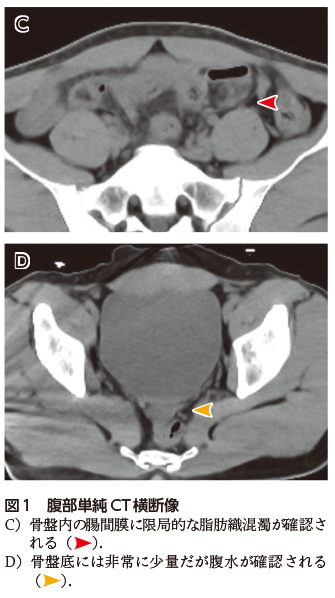

• A:骨盤底にごく少量の腹水を認める(図1D).また腸間膜に限局的な脂肪織混濁が認められる(図1C).free airや腸間膜内ガスは認めない.

ここでさっそく,今回のピットフォールを紹介する.本例は,受傷からわずか30分以内に撮影された単純CTでは,上記のような異常所見があまり顕在化していなかった.しかしその後,血圧低下と腹部膨満などを認め,超音波検査で大量の腹水が確認されたことから緊急開腹手術が行われた.術中には,腸間膜の断裂と動脈性出血,大量の血性腹水,小腸の穿孔が認められた.

なお,本例は初回のCT検査の段階で造影CT(図2として本頁にのみ掲載)も実施されており,腸間膜での造影剤の血管外漏出像(extravasation)が認められていたためすみやかに治療へと移行できた.しかし,単純CTのみで評価していた場合には,重篤性を過小評価してしまう恐れがあった.

近年,地域の救急搬送体制の整備や医療機関の対応力向上により,受傷からCT撮影までの時間が短縮されている.これは救命率の向上といった大きなメリットをもたらすが,その一方で,画像上の典型的な異常所見が顕在化する前に撮影されるケースが増加しており,注意が必要である.